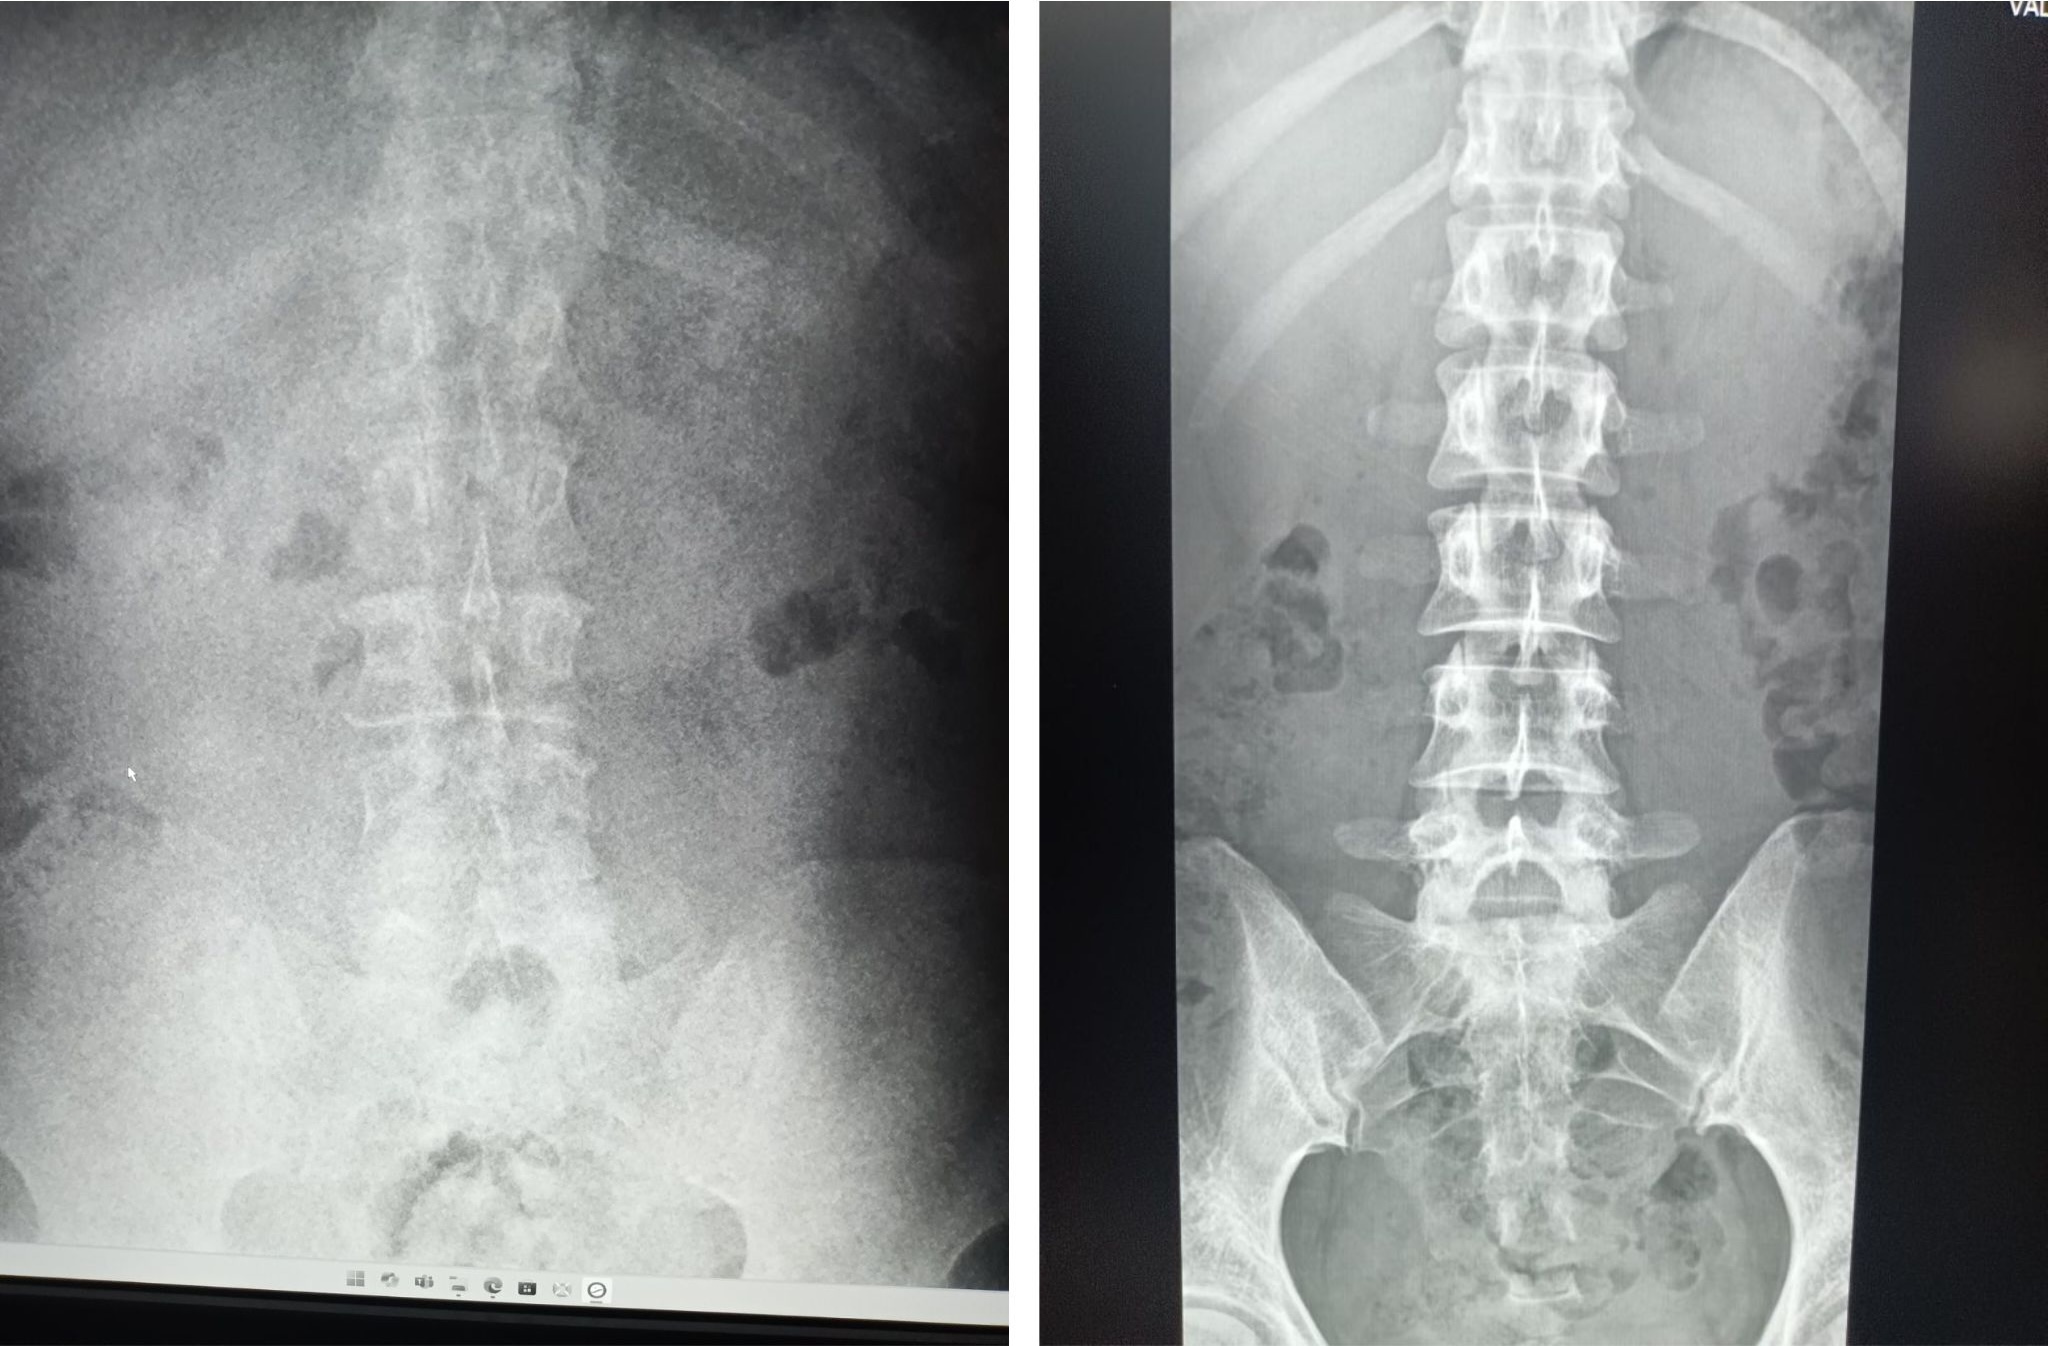

For example, while many countries have regulations around how much radiation should be used in an X-ray, there are no regulations in Palau. Not only is this unsafe for patients and staff; X-ray images taken with the wrong amount of radiation are much more difficult to interpret correctly. Dr. Hamano is raising awareness about radiation exposure and teaching technicians and doctors how to take clearer X-rays with just the right amount of radiation.